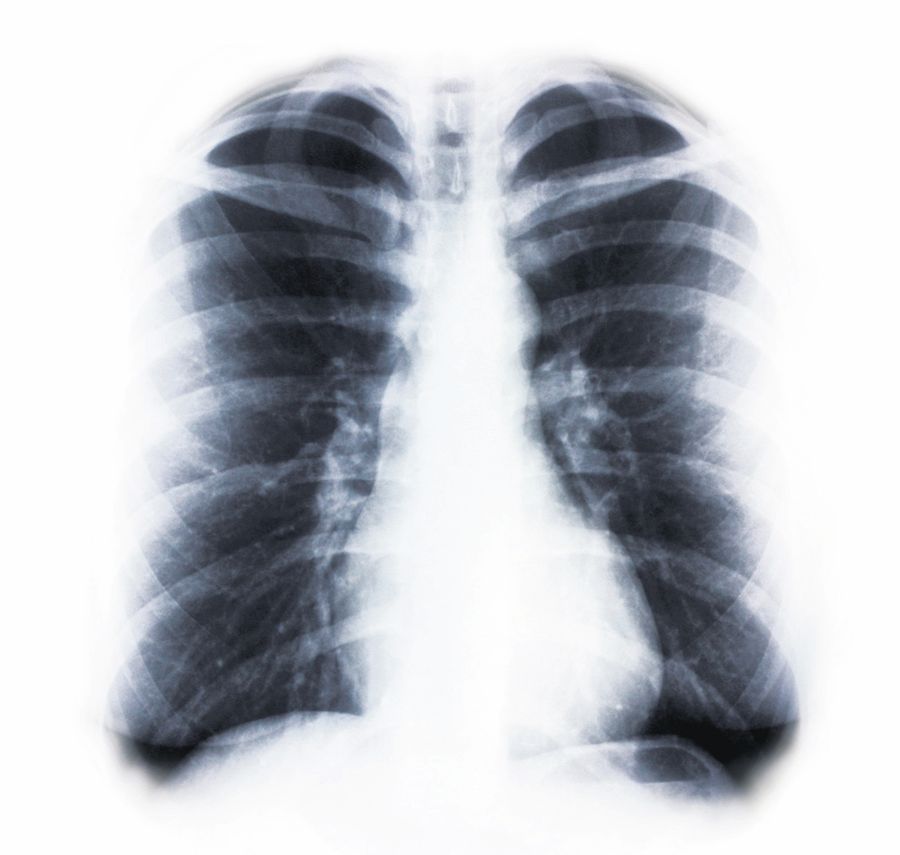

Plămânii victimelor arată ca arşi

Virusul ce a provocat moartea a sute de oameni în Ucraina ar putea fi unul mutant, susţin cercetătorii britanici care analizează în prezent tulpina virală porcină ce a declanşat epidemia din această ţară. Ei spun că germenul din Ucraina ar fi unul mult mai virulent, care atacă în special plămânii, astfel încât oamenii sunt diagnosticaţi cu pneumonie, însă autopsiile au relevat că plămânii victimelor arătau ca şi cum ar fi fost carbonizaţi.

Un doctor din vestul Ucrainei a relatat pentru ziarul britanic Daily Mail despre efectele alarmante ale virusului.

“Am făcut necropsii pe două victime şi am descoperit că plămânii lor erau negri precum cărbunele. Arătau ca şi cum ar fi fost arşi. Este înspăimântător”, a afirmat medicul a cărui identitate nu a fost făcută publică. În Ucraina au murit deja 189 de oameni şi peste un milion s-au îmbolnăvit de virusul A(H1N1), iar preşedintele Viktor Iuşcenko a apelat la Organizaţia Mondială a Sănătăţii pentru a identifica noul virus, mult mai agresiv. Rusia, Slovacia, Polonia, Ungaria şi România au instituit deja controale asupra cetăţenilor ucrainieni care intră pe teritoriul lor.